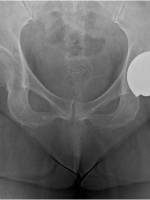

先髋的临床分类: Crowe I-IV

原则上是看股骨头位移的距离和股骨头原来高度的比例,但因为先髋的股骨头大都已经形变,所以通常是用宽股的1/5来当作股骨头的高度,所以如下图,以泪眼滴位置当做正常股骨头的低点,在把下在股骨头的低点标示出来,两者的距离(A)代表股骨头位移的距离,髋骨高度(B)的1/5或是0.2倍是股骨头原始高度,所以标准如下:

Crowe I: A/ 0.2B<0.5,股骨头位移距离小于原来股骨头高度的50%;

Crowe II: A/0.2B=0.5-0.75,股骨头位移距离占于原来股骨头高度的50-75%;

CroweIII: A/0.2B=0.75-1,股骨头位移距离占于原来股骨头高度的75-100%;

CroweIV: A/0.2B>1,股骨头位移距离大于原来股骨头高度的100%。

Crowe先髋分型如下图: